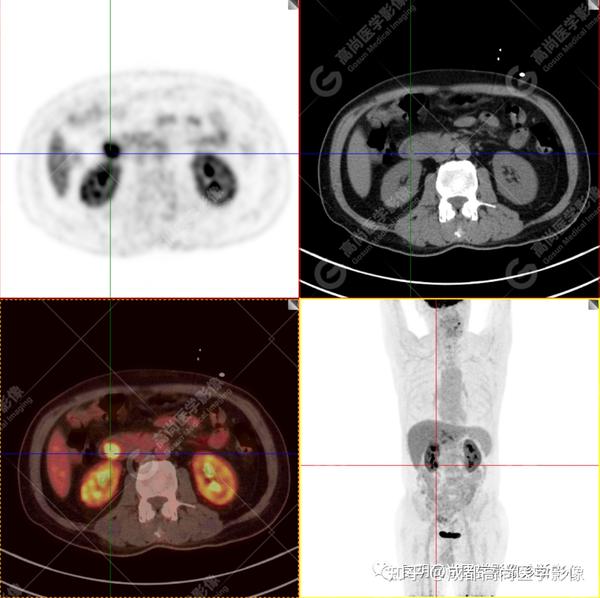

【高尚病例】壶腹周围癌——十二指肠乳头癌一例 - 知乎 By